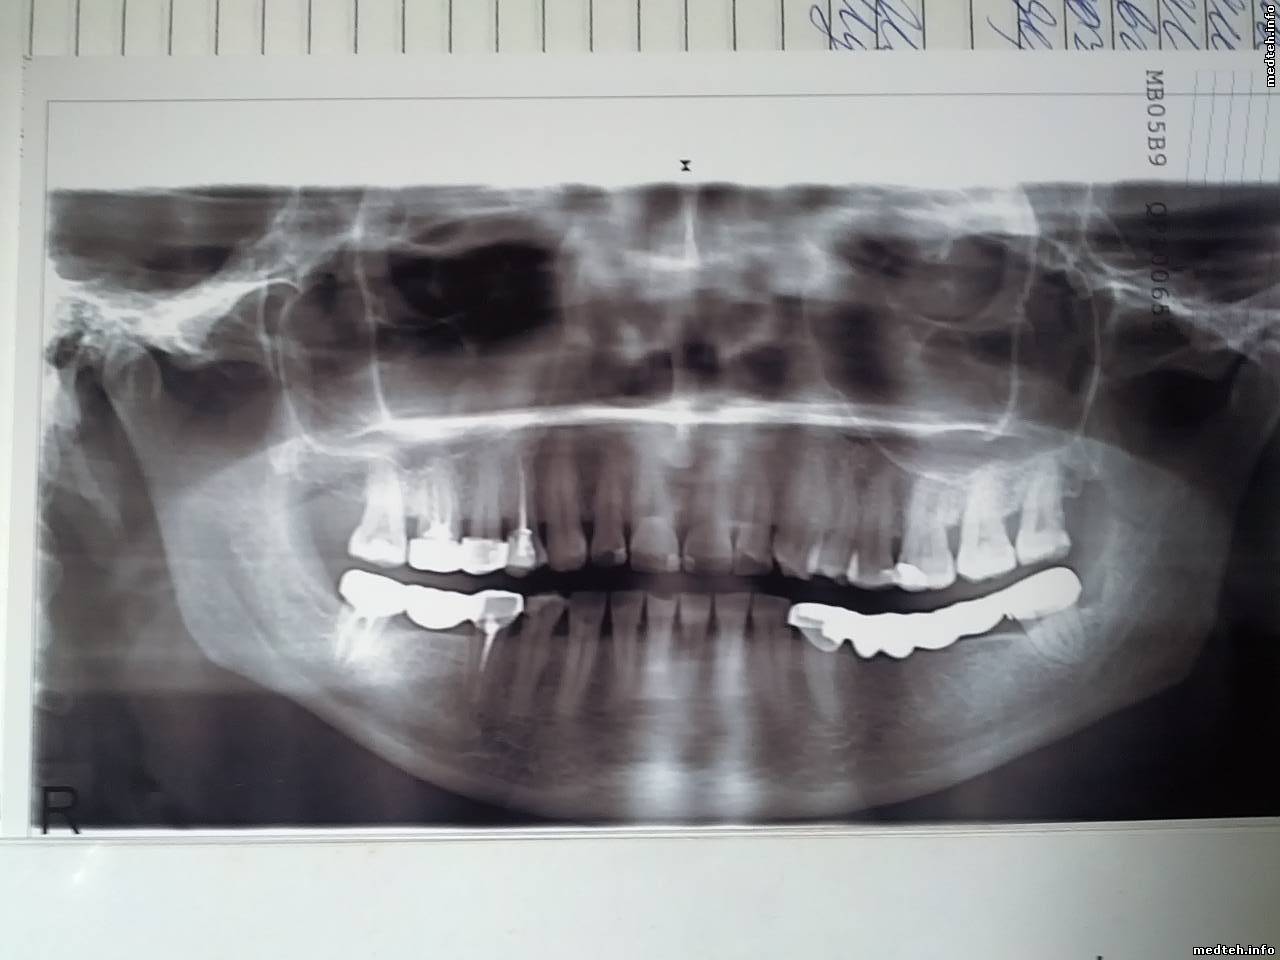

Здравствуйте коллеги. Столкнулся с такой проблемой. Двухгодовалая MORITA Veraviewepocs 2D при работе в автоматическом режиме на снимке получается черезполосица. При ручном режиме все нормально.Аппарат подключен через бесперебойник,батарея исправна. Подскажите пожалуйста причину.

Судя по снимку:

- либо челюсти стоят не на правильном месте;

- либо центр вращения системы излучатель - приёмник перемещается по неправильной траектории;

- либо самое простое - неравномерность вращения.

на снимке слева - позвоночник . shok сбита точка начала сканирования. позицирование ? руками внахалку крутили? крышку снимали?

не только тень от позвоночника. еще наклон головы назад(корни резцов не в фокусе), язык не прижат к небу.

проверить калибровки, учить лаборанта ставить пациента.

при исправном аппарате 90% качества панорамы- правильно поставить пациента.